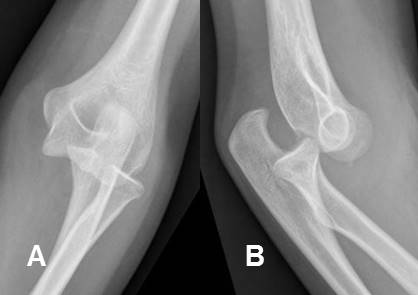

Fig 157. Luxación posterior del codo.

A: Rx AP y B: Rx lateral, que muestran luxación de las articulaciones ulnohumeral y radioulnar proximal.